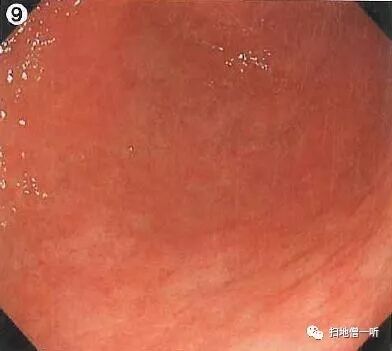

背景粘膜呈o-1型萎缩状态,弥漫性发红,大弯侧肿大的皱襞(黄框)提示HP感染。胃体中部后壁可见溃疡及皱襞集中(黑色箭头)的表现。缺乏典型恶性溃疡所见(皱襞断裂,肥大,变细,融合,蚕食像)皱襞集中趋势明显,怀疑为良性溃疡。溃疡口侧部分皱襞集中(白色箭头)并可见瘢痕性表现(白圈),考虑为慢性溃疡反复发作愈合表现。